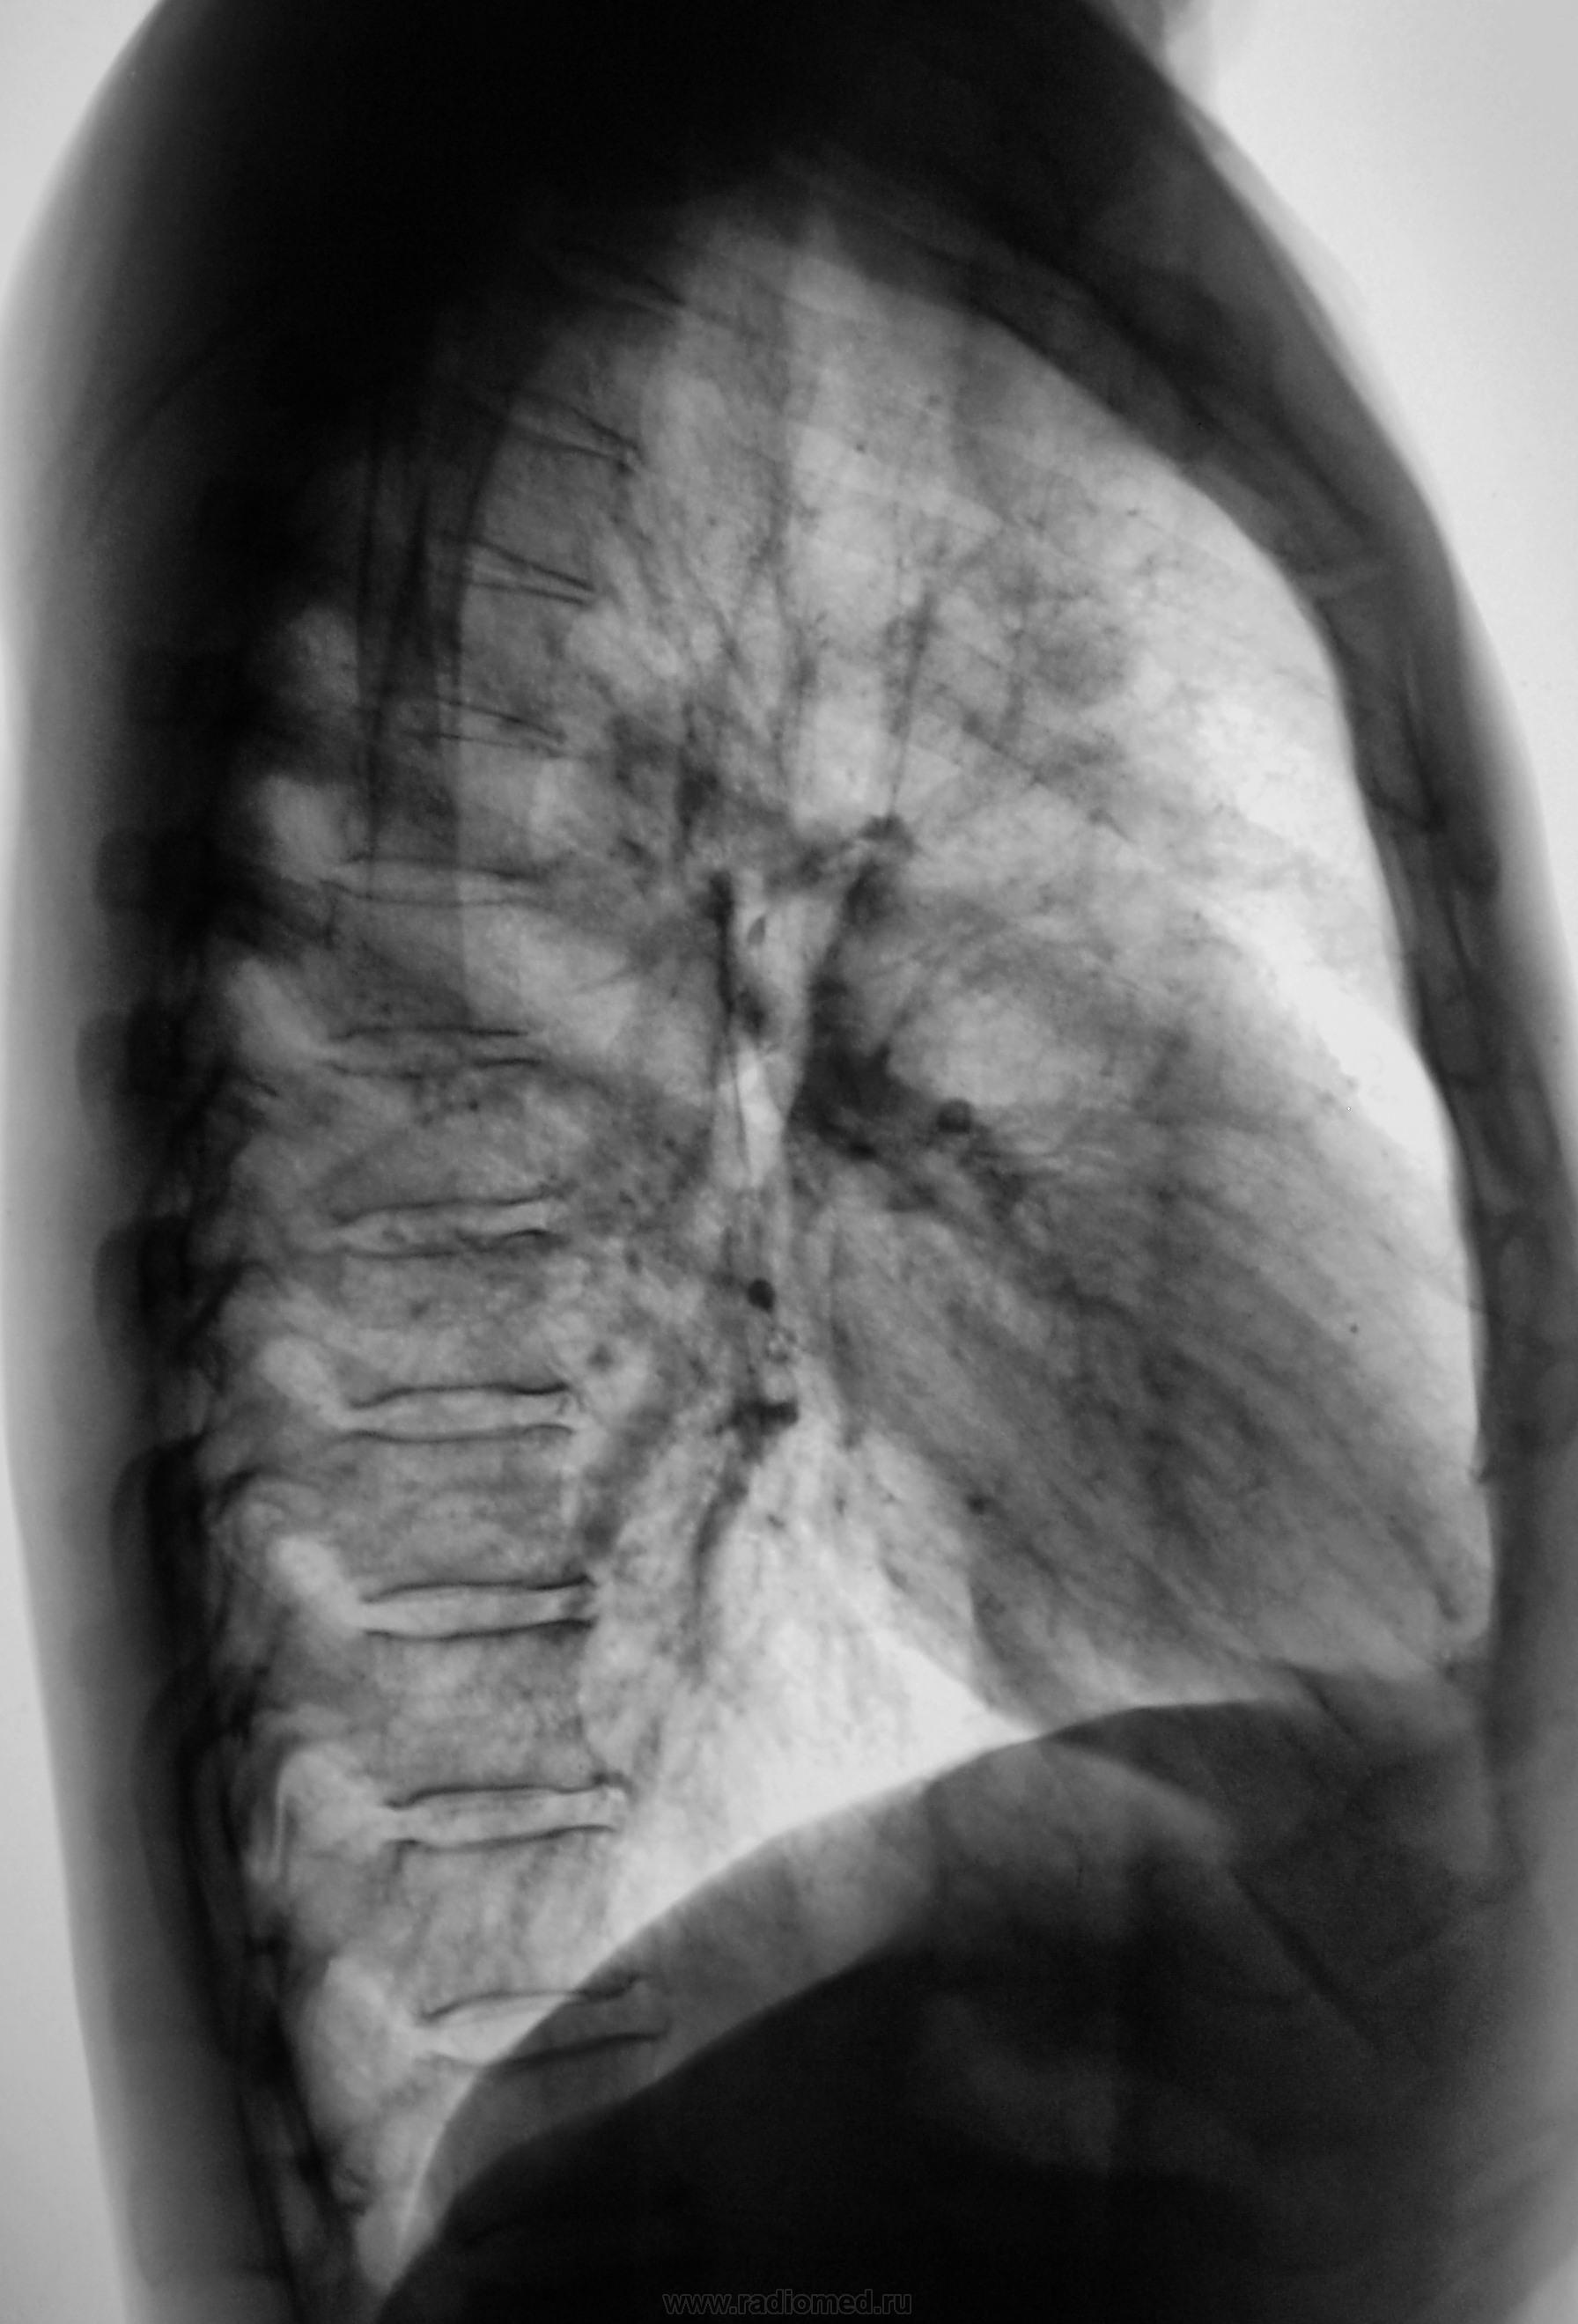

А, через 6 месяцев стало так...

1.p1190042.jpg2.p1190043.jpg3.p1190044.jpg4.p1190045.jpg5.p1190045a.jpg

Мы, после этого дообследования (последнего) упаковали пациента в ОПТД, там взяли, обнаружили палки и пациент начал лечиться

В ОПТД (вторые снимки) был выставлен инфильтративный.